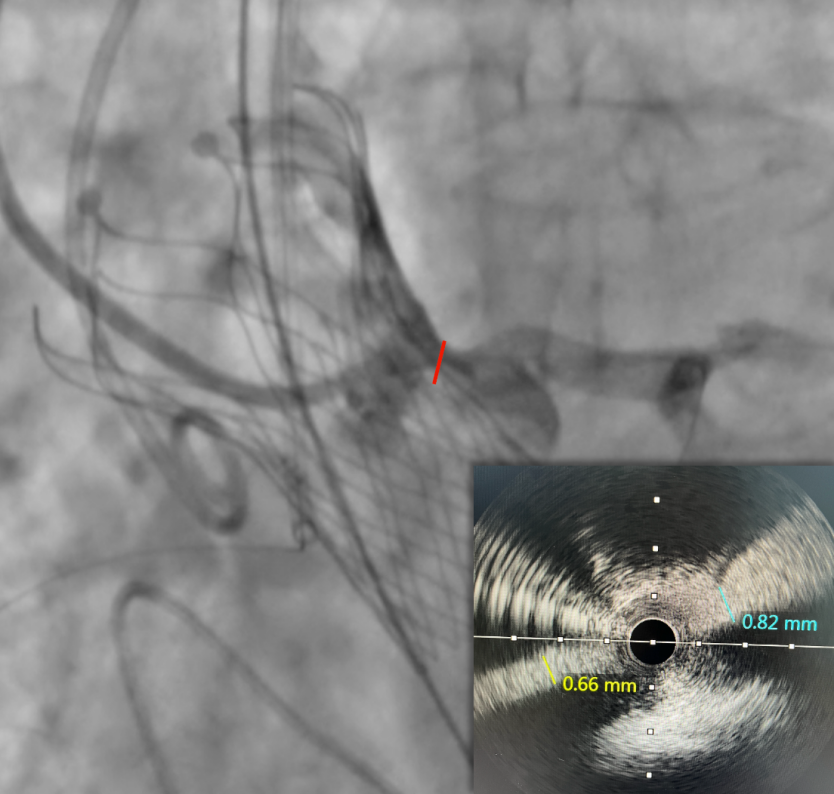

图片

IVUS检查提示因原瓣叶遮挡,左冠开口受阻,最窄处残余缝隙0.66-0.82mm。

右冠开口残余1.56mm-3.46mm,血流无明显阻挡。